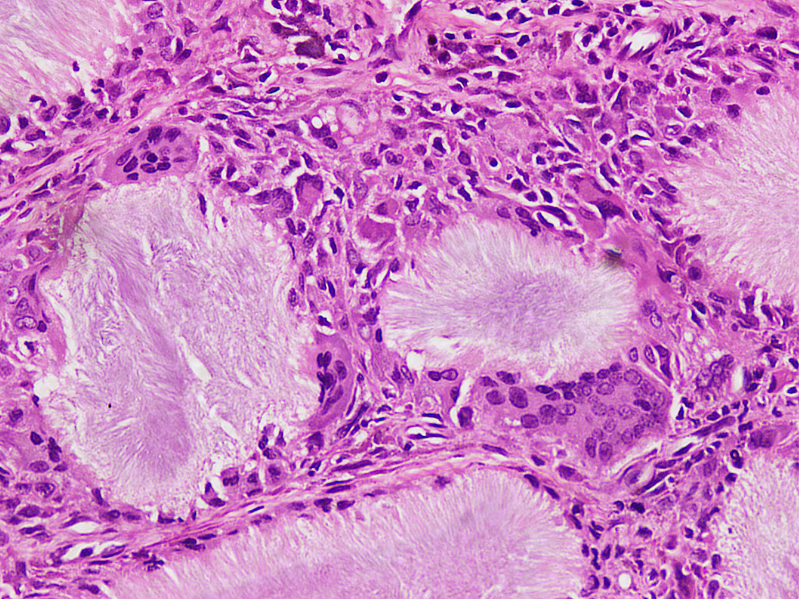

Microscopic (histologic) description

- Gout tophus:

- Nodular aggregates / granuloma-like appearance consisting of acellular, amorphous, pale eosinophilic material surrounded by palisading arrangement of histiocytes and multinucleated giant cells (Dermatol Online J 2015;21:13030)

- Feathery appearance in some deposits due to empty needle shaped spaces (Skeletal Radiol 2020;49:1325)

- Presence of monosodium urate crystals (MSU) is diagnostic

- Needle-like crystals that measure 5 - 25 micrometers in length

- Brightly anisotropic under polarized light

- Negative birefringence when examined with an interference plate in the light path (Otol Neurotol 2009;30:127)

- Crystals appear yellowish when aligned parallel to the plate axis

- Bluish appearance when alignment is across the direction of polarization

Microscopic (histologic) images